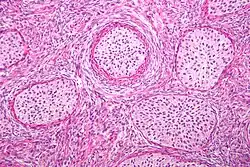

Histologically, there are nests of transitional epithelial (urothelial) cells with longitudinal nuclear grooves (coffee bean nuclei) lying in abundant fibrous stroma.

Micrograph of a Walthard cell nest, the entity Brenner tumours are thought to arise from. H&E stain.